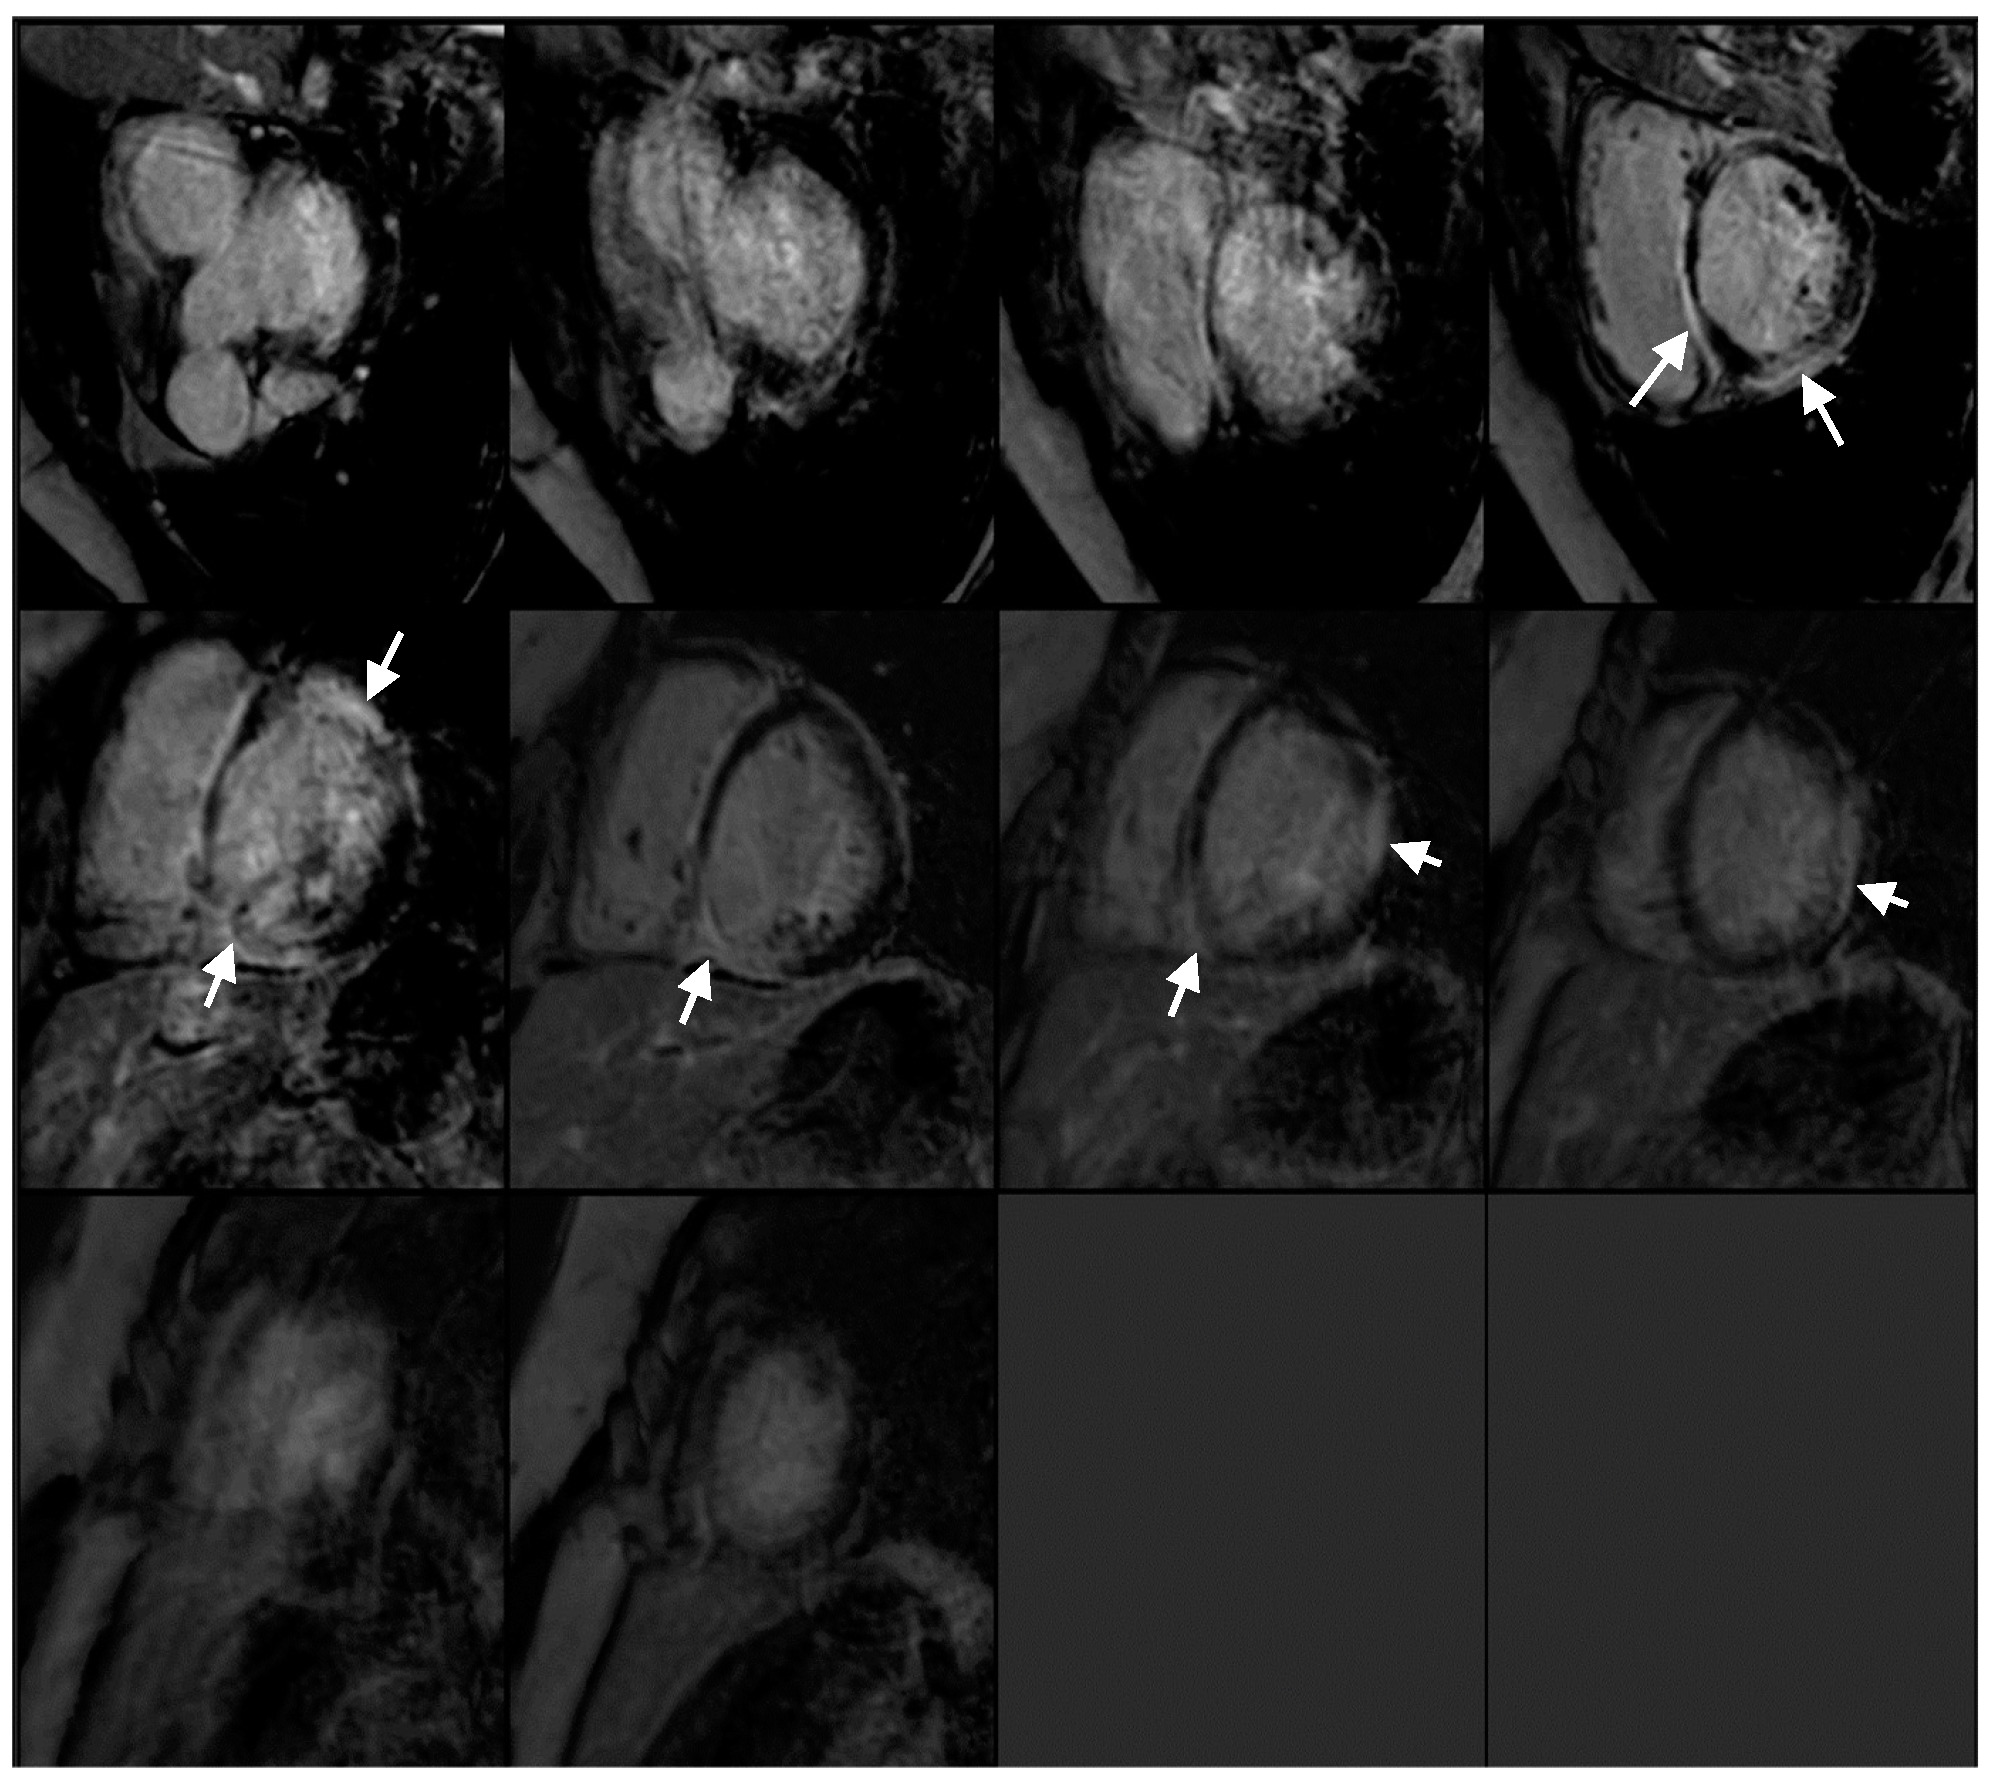

2. Case Presentation

2.1. Investigations